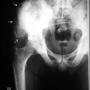

Osteosarkom

Kemik iliğinden köken alan tümörler hariç tutulduğunda, en sık görülen habis kemik tümörüdür. Normal olmayan, aşırı kemik dokusu oluşturma özelliği taşır. Yerleşim ve davranış özelliklerine bağlı tipleri vardır.

Tüm kanserler arasındaki görülme sıklığı yaklaşık %1'dir. Erkek / kadın oranı 1.5-2 / 1 dir. Genelde 10-30 yaşları arasında (%75) ve kemiklerin ekleme komşu uçlarında görülse de kemiğin herhangi bir bölgesinde ortaya çıkabilir. Giderek artan, istirahat ve ilaçla geçmeyen ağrı, sert, hareketli olmayan şişlik gibi şikayetler en sık rastlanan bulgulardır. Bir çok hasta, o bölgede daha önce herhangi bir darbe yaşandığını söylese de bu konuda herhangi bir bilimsel ilişki gösterilememiştir.